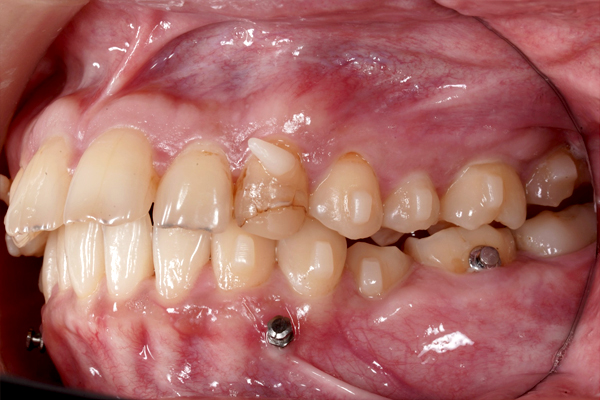

本治療では、インビザラインを用いた非抜歯矯正を行っています。治療の進行にあわせて、インプラントアンカーを使用し、歯を後方へ移動させる計画です。治療期間はおよそ1年6か月を予定しており、現在は開始から9か月が経過した段階です。

横からの比較(右側)

横からの比較(左側)